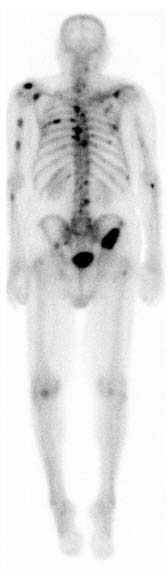

A nuclear medicine whole-body bone scan. The nuclear medicine whole-body bone scan is generally used in evaluations of various bone-related pathology, such as for bone pain, stress fracture, nonmalignant bone lesions, bone infections, or the spread of cancer to the bone.

A bone scan or bone scintigraphy /sɪnˈtɪɡrəfi/ is a nuclear medicine imaging technique of the bone. It can help diagnose a number of bone conditions, including cancer of the bone or metastasis, location of bone inflammation and fractures (that may not be visible in traditional X-ray images), and bone infection (osteomyelitis).[1]